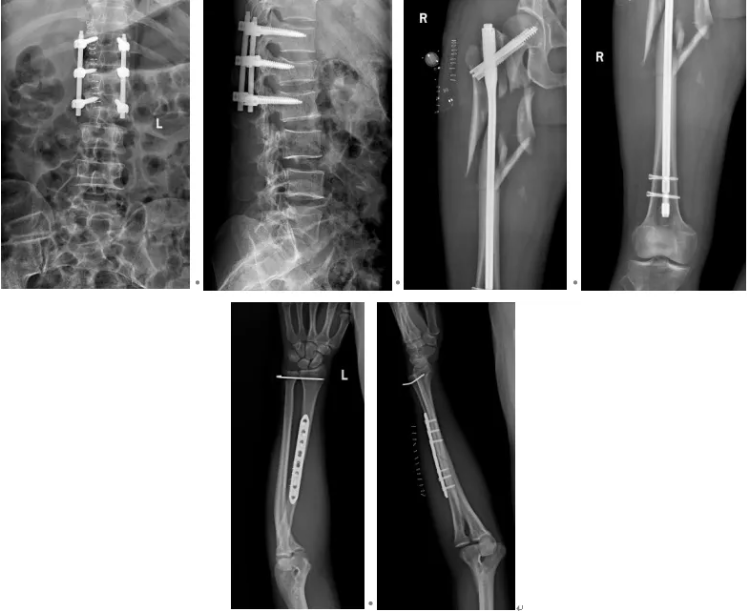

6月9日,为患者实施右股骨、左桡骨、腰 1 椎体爆裂性骨折复位内固定术,同时对左股骨远端开放性骨折再次清创,确认伤口无感染迹象,基底长出新鲜肉芽组织;

8月7日,动态监测显示患者各项炎症指标逐步下降,多次分泌物培养均无细菌生长,床旁拆除外固定架,改用左下肢支具保护;

8月26日,实施开放性左股骨远端粉碎性骨折坏死组织切除性清创术,取出原有内固定物,采用万古霉素抗生素骨水泥钢板内固定术,彻底稳固骨折部位。

术后,为患者提供镇痛、消肿、预防感染及下肢深静脉血栓等综合治疗,并指导其开展左膝关节屈伸功能锻炼。经过近3个月的系统救治与康复,患者各切口愈合良好,肢体功能基本恢复,顺利达到出院标准。